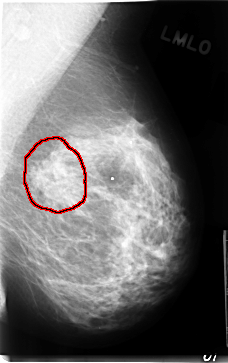

C_0080_1.LEFT_MLO

LEFT_MLO LINES 4712 PIXELS_PER_LINE 2960 BITS_PER_PIXEL 12 RESOLUTION 50 OVERLAY

FILE: C_0080_1.LEFT_MLO.OVERLAY

TOTAL_ABNORMALITIES 1

ABNORMALITY 1

LESION_TYPE MASS SHAPE IRREGULAR MARGINS ILL_DEFINED

ASSESSMENT 4

SUBTLETY 2

PATHOLOGY MALIGNANT

TOTAL_OUTLINES 1

BOUNDARY